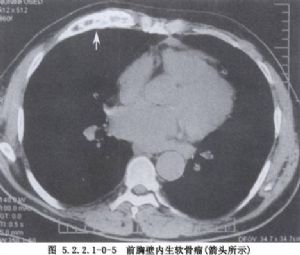

除病史及體格檢查外,還要攝胸部X線片,斷層攝影等必要的檢查。胸壁軟組織腫瘤X線片的特點爲陰影密度不高。切線位片瘤體中心位於側胸壁,瘤體與胸壁成鈍角。骨良性腫瘤一般爲圓形、橢圓形,骨皮質無斷裂。骨軟骨瘤常見在肋骨骨髓區內,頂部呈圓形或菜花狀,境界銳利,有不規則鈣化軟骨帽,瘤內有點狀鈣化。軟骨瘤常發生在肋骨與肋軟骨交界處,腫瘤有分葉,受累骨膨脹,骨皮質變薄,內有點狀鈣化,難與軟骨肉瘤鑑別。骨纖維結構不良,常發生在後側肋骨,始自嬰幼兒期,常到青壯年才發現,病竈呈侷限性膨大,骨皮質變薄,病變區呈磨玻璃樣變。肋骨骨鉅細胞瘤有皁泡狀透亮區,骨皮質薄如蛋殼。惡性腫瘤X線所見,主要爲侵蝕性骨破壞,呈篩孔樣、蟲蝕樣,可見溶骨或成骨性改變,邊緣較毛糙,骨皮質缺損、中斷或病理性骨折。軟骨肉瘤起自骨髓部分,呈分葉狀腫塊,邊緣不清,內有點狀或斑狀鈣化竈。骨肉瘤X線表現分爲溶骨型、成骨型及混合型3種。成骨型有放射狀排列的新生針狀骨小梁,邊界不清。Ewing肉瘤佔原發性胸壁骨腫瘤的12%,X線片見骨呈斑片狀破壞,含有溶骨和增生區,骨膜增生呈層狀,稱“蔥皮”樣改變。MRI可將腫瘤與血管區別,應採用不同平面瞭解腫瘤情況。活檢是診斷的可靠方法,應注意惡性腫瘤常有良性部分,多部位、足夠組織取材是正確診斷的關鍵。胸壁腫瘤的診斷十分重要,它決定治療方法的選擇(圖5.2.2.1-0-1~5.2.2.1-0-5)。